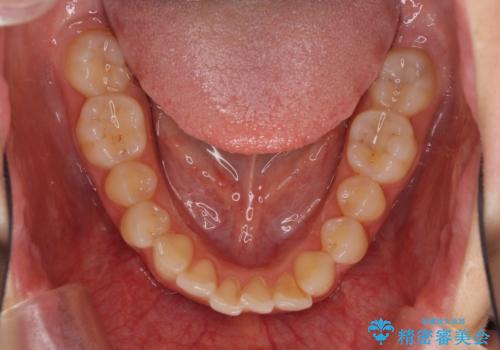

口が閉じにくい 1本飛び出した前歯の矯正治療

- 1本飛び出した前歯を治したいとのことで来院された患者様です。

歯列全体の拡大とIPR(歯と歯の間を削る)によってデコボコが解消するようにし、さらにゴムかけを活用して右側の咬み合わせ位置を変えるように設計し、インビザラインにより治療を行うこととしました。